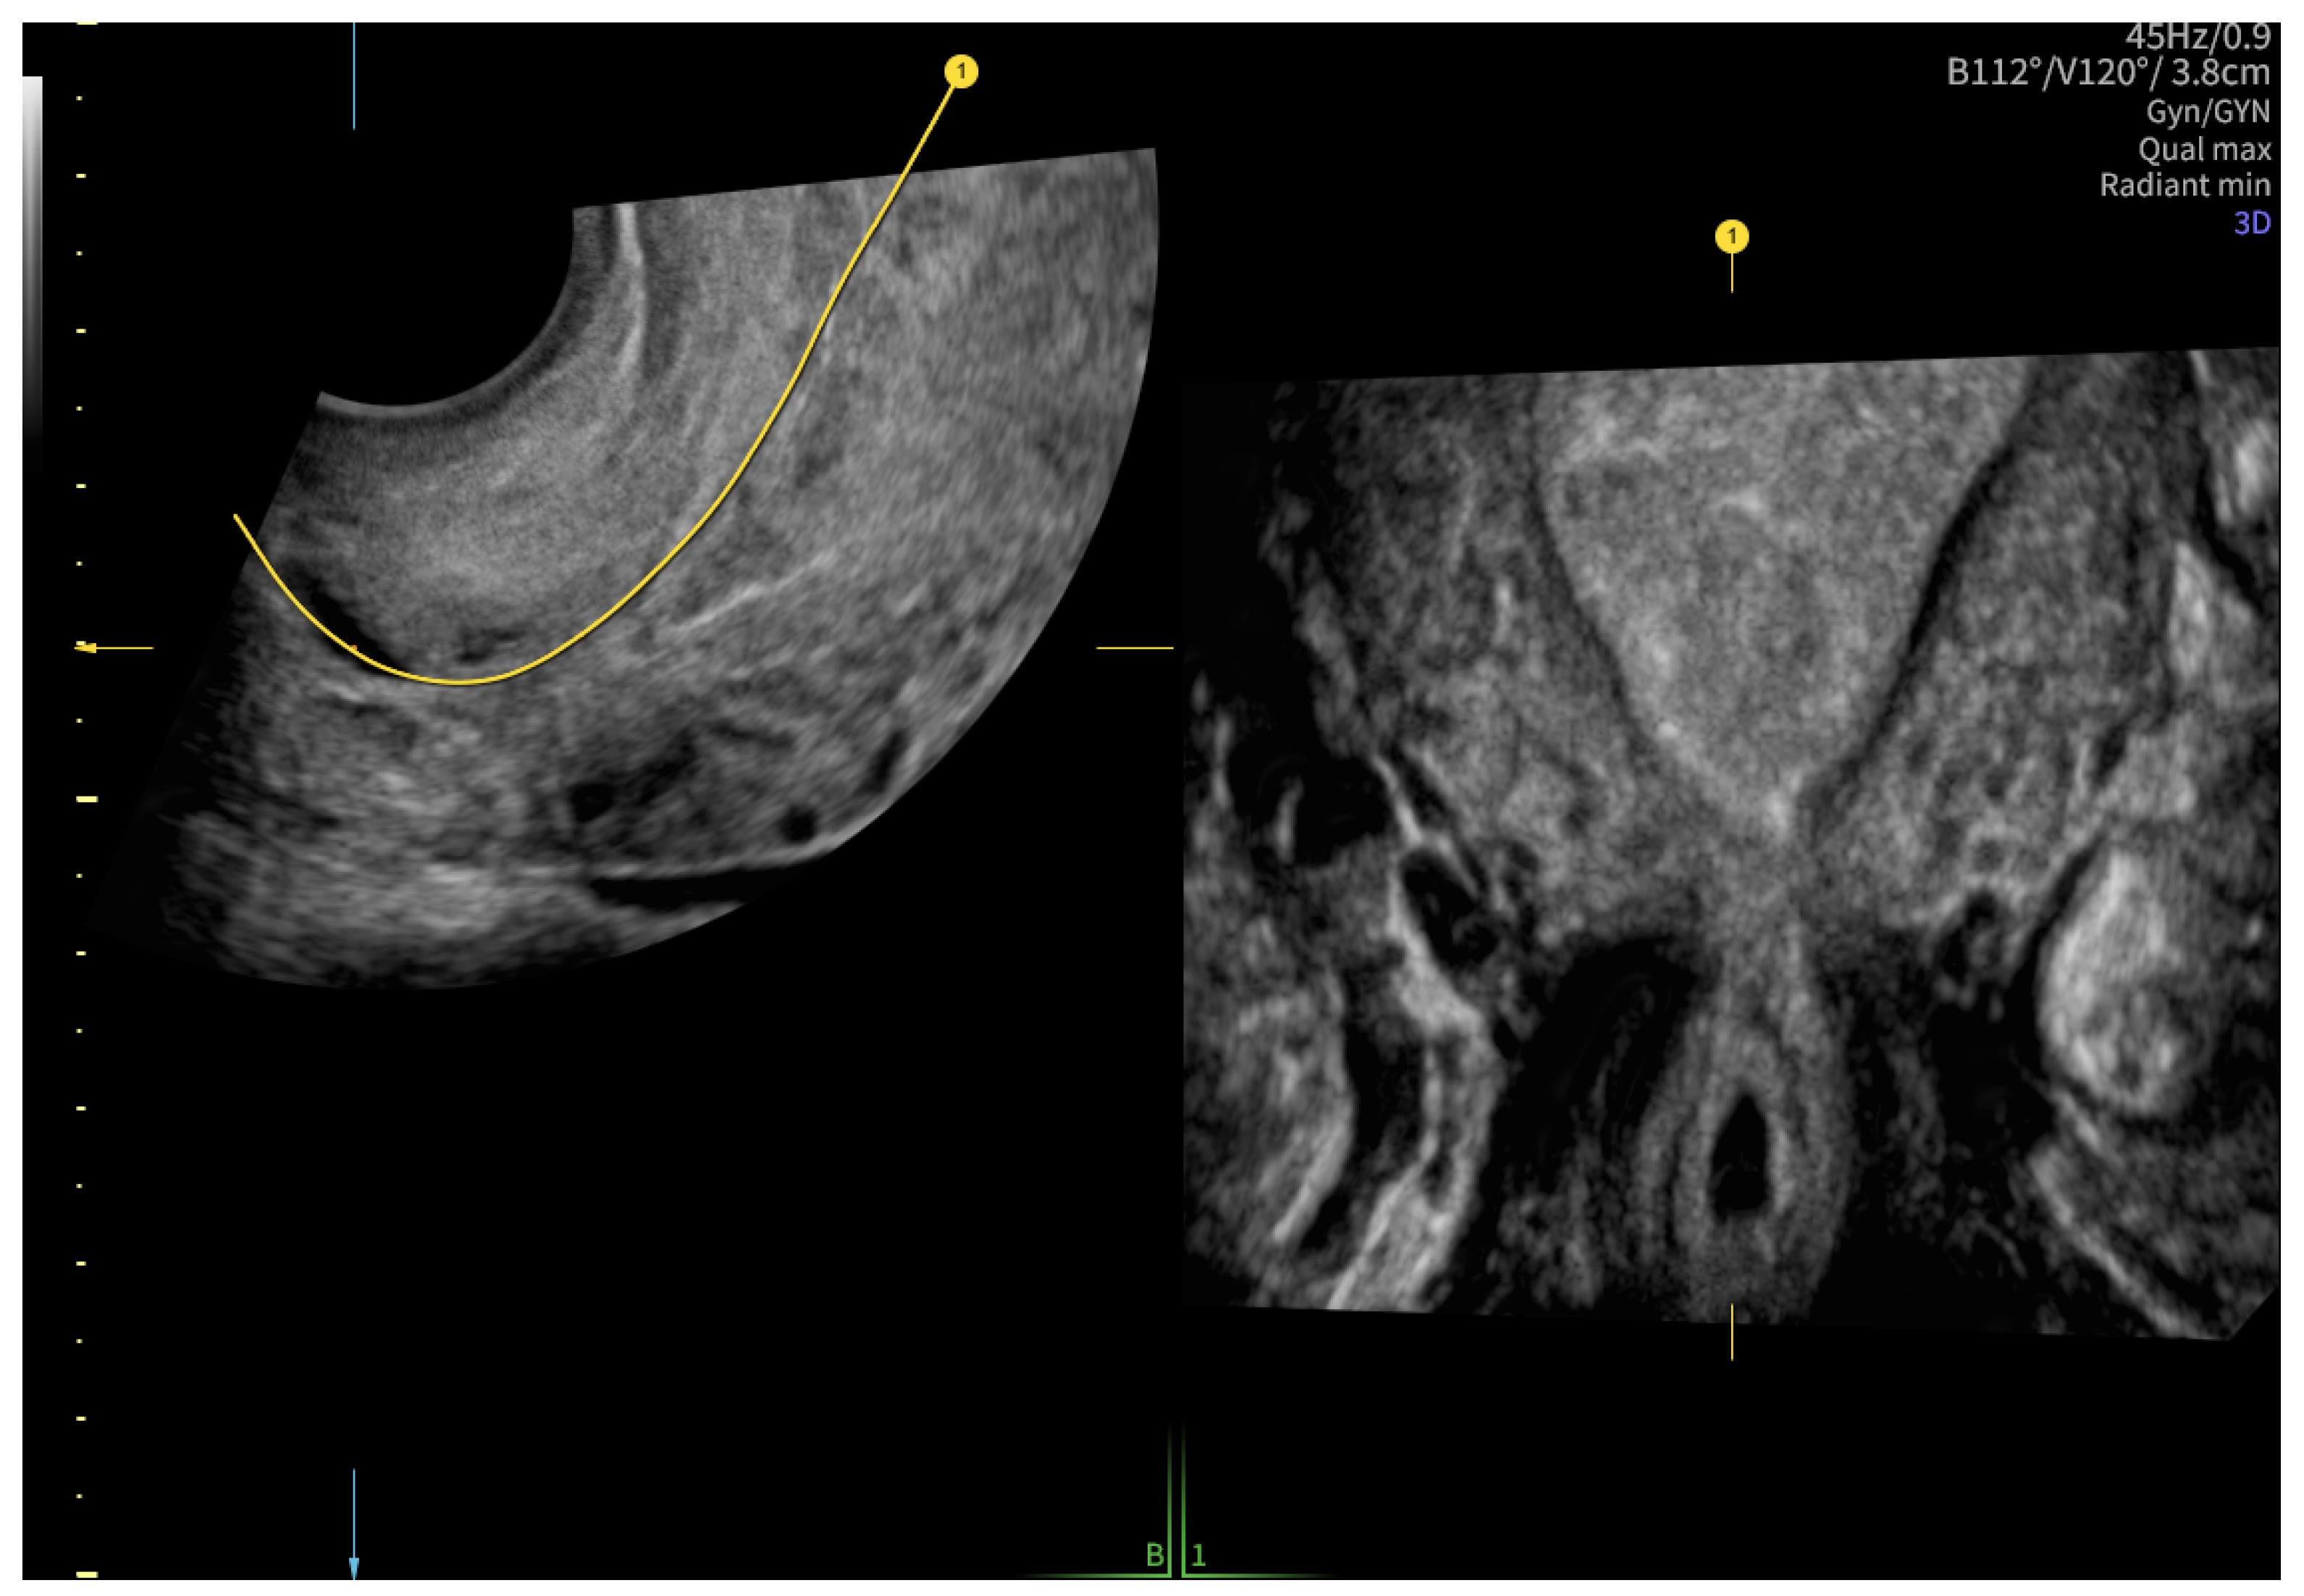

2. Case Presentation